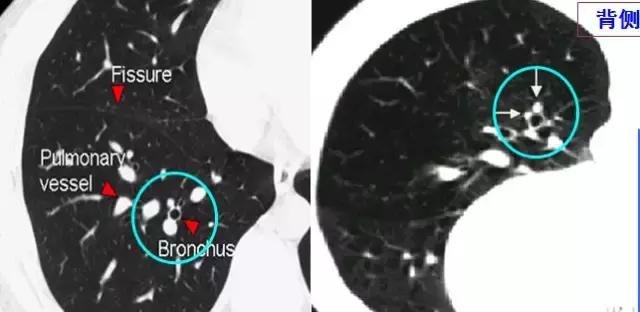

CT征象二:轨道征与印戒征

1、“轨道征”:扩张支气管走行与CT扫描平面平行时

2、“印戒征”:扩张支气管与CT扫描层面垂直时

(正常同级别的肺动脉直径稍大于伴行的支气管内径)

CT表现:在肺野内显示为平行的线样高密度影或环形低密度影伴周围点状高密度影(直径小于前者)

意义:表明有支气管扩张、慢性支气管炎伴发的细支气管扩张等。

柱状支气管扩张与扫描层面垂直——“印戒征”